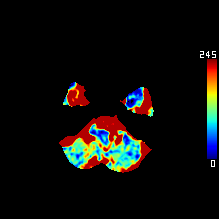

DeepClue-Precise CT 측부혈류영상

Perfusion CT를 이용한 측부혈류영상

동맥기

모세혈관기

조기정맥기

후기정맥기

지연기

조기정맥기까지 남은 허혈 영역 : 초기 뇌경색 영역과 일치 (일치율 0.97)

모세혈관기의 허혈 영역 : 허혈반음영을 반영 (일치율 0.89)